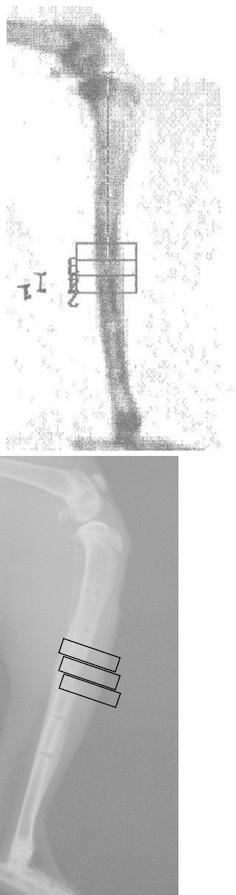

Evaluation of the material properties of regenerate bone is of fundamental importance to a successful outcome following distraction osteogenesis using an external fixator. Plain radiographs are in widespread use for assessment of alignment and the distraction gap but are unable to detect bone formation in the early stages of distraction osteogenesis and do not quantify accurately the structural properties of the regenerate. Dual X-ray absorptiometry (DXA) is a widely available non-invasive imaging modality that, unlike X-ray, can be used to measure bone mineral content (BMC) and density quantitatively. In order to be useful as a clinical investigation; however, the structural two-dimensional geometry and density distributions assessed by DXA should reflect material properties such as modulus and also predict the structural mechanical properties of the regenerate bone formed. We explored the hypothesis that there is a relationship between DXA assessment of regenerate bone and structural mechanical properties in an animal model of distraction osteogenesis. Distraction osteogenesis was carried out on the tibial diaphysis of 41 male, 12 week old, New Zealand white rabbits as part of a larger study. Distraction started after a latent period of 24 h at a rate of 0.375 mm every 12 h and continued for 10-days, achieving average lengthening of 7.1 mm. Following an 18-day period of consolidation, the regenerate bone was subject to bone density measurements using a total body dual-energy X-ray densitometer. This produced measurement of BMC, bone mineral density (BMD) and volumetric bone mineral density (vBMD). The tibiae were then disarticulated and cleaned of soft tissue before loading in compression to failure using an Instron mechanical testing machine (Instron Corporation, Massachusetts USA). Using Spearman rank correlation and linear regression, there was a significant correlation between vBMD and the Modulus of Elasticity, Yield Stress and Failure Stress of the bone. No correlation was seen between BMC, BMD, vBMR and any mechanical parameter. DXA is a promising tool for the assessment of regenerate bone formed by DO during limb lengthening and requires further investigation.

评估再生骨的材料特性对于使用外固定器进行牵张成骨术后的成功结果至关重要。普通X线平片广泛用于评估对线和牵张间隙,但无法在牵张成骨的早期阶段检测到骨形成,也不能准确量化再生骨的结构特性。双能X线吸收法(DXA)是一种广泛应用的非侵入性成像方式,与X线不同,它可用于定量测量骨矿物质含量(BMC)和骨密度。然而,为了作为一项临床研究有用;通过DXA评估的二维结构几何形状和密度分布应反映诸如模量等材料特性,并预测所形成的再生骨的结构力学性能。我们探讨了在牵张成骨动物模型中,DXA对再生骨的评估与结构力学性能之间存在关联的假设。作为一项更大研究的一部分,在41只12周龄的雄性新西兰白兔的胫骨干进行牵张成骨。在24小时的潜伏期后开始牵张,以每12小时0.375毫米的速度持续10天,平均延长7.1毫米。在18天的巩固期后,使用全身双能X线骨密度仪对再生骨进行骨密度测量。这得出了BMC、骨矿物质密度(BMD)和体积骨矿物质密度(vBMD)的测量值。然后将胫骨关节离断并清除软组织,再使用英斯特朗材料试验机(美国马萨诸塞州英斯特朗公司)进行压缩加载直至破坏。使用Spearman等级相关性和线性回归分析,vBMD与骨的弹性模量、屈服应力和破坏应力之间存在显著相关性。未观察到BMC、BMD、vBMR与任何力学参数之间存在相关性。DXA是评估肢体延长过程中牵张成骨形成的再生骨的一种有前景的工具,需要进一步研究。